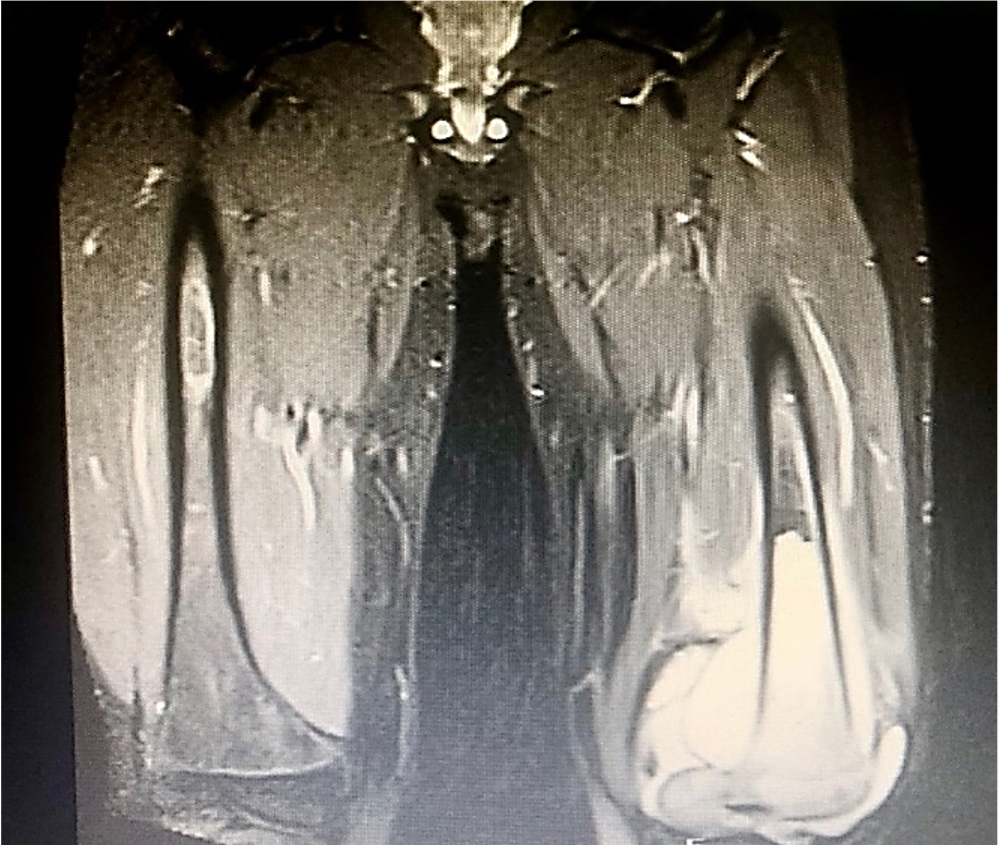

En la radiografía de miembro inferior izquierdo (MII) se aprecia disminución del espacio femorotibial interno con reacción perióstica cortical anterior en tercio distal del fémur y triangulo de Codman (Ver figura 1). En la resonancia magnética nuclear (RMN) de MII con contraste, se observa una lesión de aspecto tumoral a nivel distal del fémur y compromiso del núcleo de crecimiento medial e hidroartrosis (Ver Figura 2). En la gammagrafía ósea se aprecian lesiones blásticas hipercaptantes en diáfisis proximal de humero derecho, espina iliaca anteroinferior, fémur en su diáfisis distal, rotula y tibia izquierda (Ver figura 3). La tomografía axial computarizada (TAC) de tórax y abdomen contrastado fue reportada como normal. El ecocardiograma doppler también fue reportado como normal.

Figura 2. RNM de MIII con contraste.

Lesión de aspecto tumoral a nivel distal del fémur, con compromiso del núcleo de crecimiento medial e hidroartrosis. Figura 3.

Figura 4. RNM de fémur comparativa

Lesión tumoral hiperintensa con calcificación a nivel periostal del fémur de origen infiltrativo y con aumento de partes blandas por proceso neoplásico, compromete el núcleo de crecimiento medial del fémur a nivel periostótico con captación diseminada del material de contraste. Cambio osteopénicos y edema de y tejidos blandos.